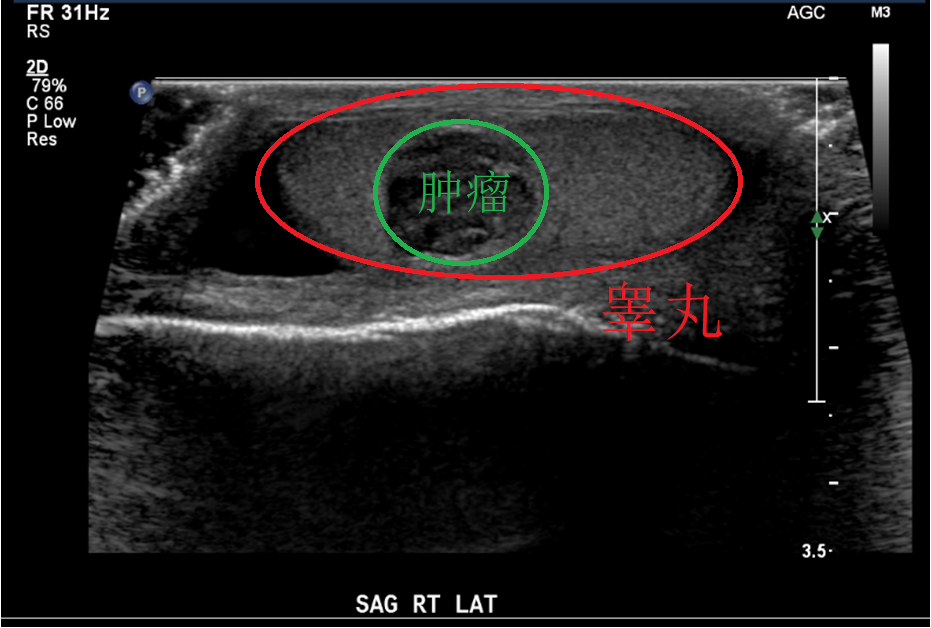

超声检查只能发现有没有睾丸肿瘤,是不能有效鉴别良恶性的。当然无回声的囊性病变多是良性,边界清楚、低血流的病变也多是良性。

上图:睾丸肿瘤的超声表现

有些睾丸肿瘤被超声发现时是很小的,两侧的睾丸大小还是基本上对称的,医生查体也根本感受不到,能在早期被查到,那是不幸中的万幸。